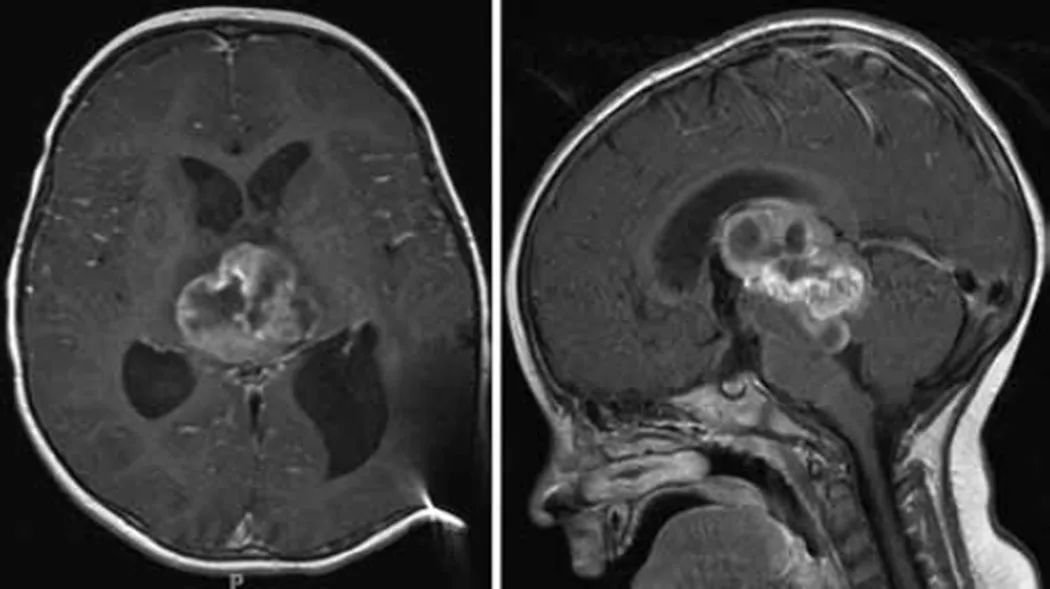

36岁的晴晴在2021年11月因鼻炎进行颅脑CT检查,显示松果体占位性病变,当时大小为16*15*12mm,无特别神经功能障碍,随后进行颅脑核磁MRI,医生建议先观察3个月。观察结束后进行复查,建议手术治疗并告知相关风险。考虑到手术风险,晴晴选择继续保守治疗。2022年9月再次复查,肿瘤伴幕上脑积水。除了偶有眩晕、脑涨,其他症状并不明显,晴晴还是选择了保守。2023年3月再次复查时,肿瘤竟然长大了18*18*15mm,并出现幕上脑积水。临床症状不变化,医生建议再持续观察3-6月,但最终需要手术治疗。

在首都医科大学附属北京天坛医院,巴教授成功主刀完成这台交流手术,手术全切肿瘤。术后即清醒,无新发神经损伤。术后1周后,术后病理结果为WHO2-3级中分化松果体实质肿瘤,根据巴教授建议患者及时进行放化疗,巴教授及时全切手术为后续放化疗争取到了更好的结果。点击阅读:天坛医院手术纪实 | 高知精英的她,高难度开颅术后18月恢复如何?